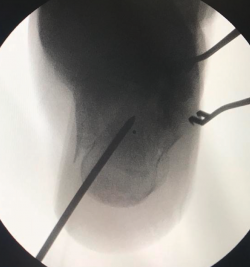

Cuando tenemos todos los fragmentos en su posición anatómica, habiéndose conseguido la reducción de la superficie subastragalina posterior, se fijan de manera provisional dichos fragmentos con agujas de Kirschner (aK) de 1,0 o 1,2. Estas aK fijan los fragmentos laterales de la fractura a la zona medial que normalmente está intacta. Se comprueba bajo fluoroscopio (proyección lateral) que se ha restablecido el ángulo de Böhler (Figura 3) y se fija de forma definitiva con 2 o 3 tornillos canulados de lateral a medial.

Figura 3. Varón de 59 años con fractura del calcáneo de Sanders de tipo IIA tras caída de 2 m de altura. Ángulo de Böhler precirugía de 6,3°, ángulo de Böhler poscirugía de 20,7° y a los 3 meses de 22,3°. No presentó ninguna complicación.